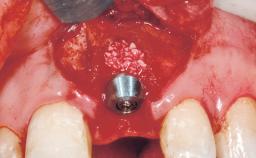

A 39-year-old male patient presented with a chief complaint of discomfort and gingival discoloration around his maxillary left central incisor. He was in good general health and was a non-smoker. His past dental history was significant because of the traumatic fracture of tooth 21 in a sporting accident at age 13. Initial dental treatment included endodontic therapy and a full-coverage restoration. The patient became symptomatic 5 years later, when structural failure of the tooth resulted in the dislodgment of the crown. Endodontic retreatment, apical surgery, and post-and-core restoration were performed.

Type of Implants One-Piece

Attachment One-Piece

Placement Protocol Early or late implant placement